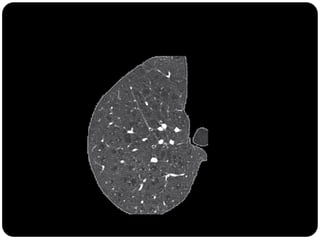

Pequeno nódulo no pulmão direito

Pequeno nódulo nopulmão direito